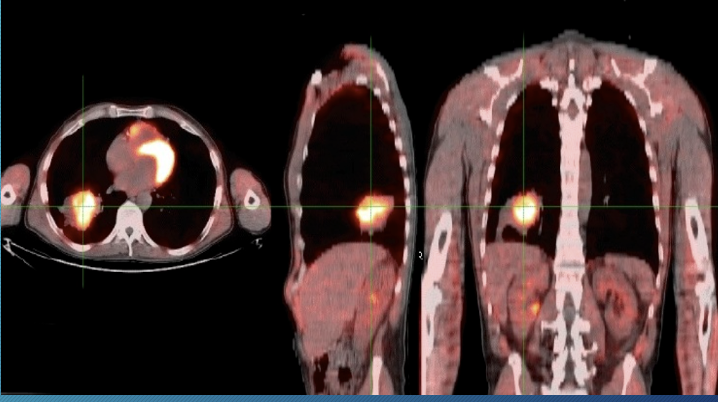

Positron emission tomography (PET) scan

marker of active glucose metabolism and will accumulate in metabolically active tumor cells

90% sensitivity, 85% specificity

-false negative: small nodule < 8mm, carcinoid, BAC

-false positive: granulomatous infection/inflammation